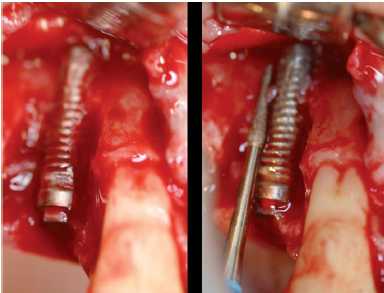

— En las prótesis atornilladas, debemos levantar el composite

y patología perimplantaria (Figuras 9a y 9b).

Figuras 9a y 9b. Relleno de gutapercha y composite de las chimeneas